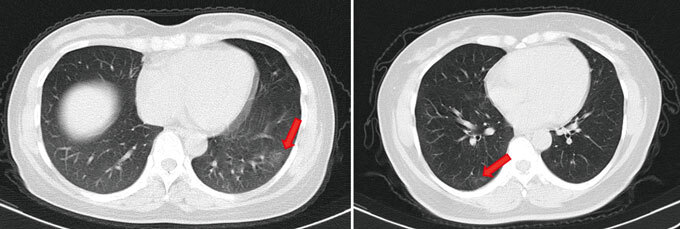

Even those who seem to pass through a SARS-CoV-2 infection without a sniffle may not come out unscathed. Researchers assessed 37 people who tested positive for the coronavirus but didn’t have symptoms in the two weeks before their test or during their isolation in the Wanzhou People’s Hospital in China. Twenty-one had abnormal features in their lungs that have been seen in patients with COVID-19 pneumonia, the researchers report online June 18 in Nature Medicine.

That leaves open the possibility that asymptomatic people, not just those with symptoms, may end up with long-term consequences. “One of the concerns is, are these people going to be left with lungs that don’t function normally?” Malani says.